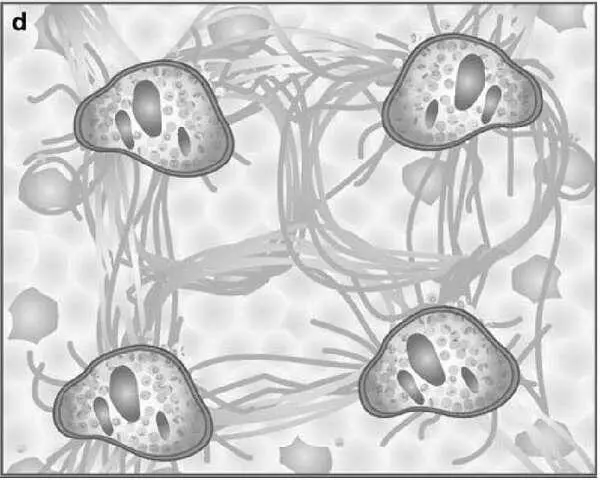

Рисунок 6 – Схемы формирования фиброза печени (по Batts KP, Ludwig J.)

На рис. 6 представлены диаграммы, отражающие последовательность развития фиброза в печени при гепатите. Представлены 4 стадии болезни печени: а – фиброз портальных трактов, b – септы, распространяющиеся от портальных трактов и местами соединяющие их; c – трансформация в цирроз печени, когда в некоторых участках исследуемого образца отмечаются формирующиеся узлы регенерации; d – окончательно сформированный цирроз печени.